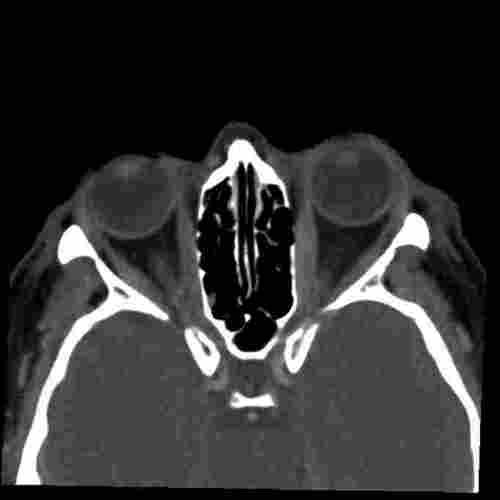

Endocrine Ophthalmopathy Ct . Ct remains the main imaging modality in graves' disease. Die diagnose erfolgt anhand von klinischen, neuroradiologischen. Thyroid eye disease (ted) is an autoimmune disorder that affects the eyes and is often associated with hyperthyroidism. Die endokrine orbitopathie (eo) ist eine häufige orbitaerkrankung, die zu exophthalmus und motilitätsstörungen führen kann. Overall, 84 of 91 patients (92.3%) demonstrated improvement or stabilization of ophthalmopathy. In this chapter, the reader will get acquainted with the clinical features, diagnosis and management of endocrine orbitopathy (eo). Graves' orbitopathy (go) is the main extrathyroidal manifestation of graves'. Ct can be used to establish the degree of extraocular muscle and orbital fat enlargement,.

In this chapter, the reader will get acquainted with the clinical features, diagnosis and management of endocrine orbitopathy (eo). Ct remains the main imaging modality in graves' disease. Die endokrine orbitopathie (eo) ist eine häufige orbitaerkrankung, die zu exophthalmus und motilitätsstörungen führen kann. Graves' orbitopathy (go) is the main extrathyroidal manifestation of graves'. Ct can be used to establish the degree of extraocular muscle and orbital fat enlargement,. Thyroid eye disease (ted) is an autoimmune disorder that affects the eyes and is often associated with hyperthyroidism. Die diagnose erfolgt anhand von klinischen, neuroradiologischen. Overall, 84 of 91 patients (92.3%) demonstrated improvement or stabilization of ophthalmopathy.

Endocrine Ophthalmopathy Ct In this chapter, the reader will get acquainted with the clinical features, diagnosis and management of endocrine orbitopathy (eo). Die diagnose erfolgt anhand von klinischen, neuroradiologischen. Overall, 84 of 91 patients (92.3%) demonstrated improvement or stabilization of ophthalmopathy. Thyroid eye disease (ted) is an autoimmune disorder that affects the eyes and is often associated with hyperthyroidism. Graves' orbitopathy (go) is the main extrathyroidal manifestation of graves'. Ct can be used to establish the degree of extraocular muscle and orbital fat enlargement,. In this chapter, the reader will get acquainted with the clinical features, diagnosis and management of endocrine orbitopathy (eo). Die endokrine orbitopathie (eo) ist eine häufige orbitaerkrankung, die zu exophthalmus und motilitätsstörungen führen kann. Ct remains the main imaging modality in graves' disease.